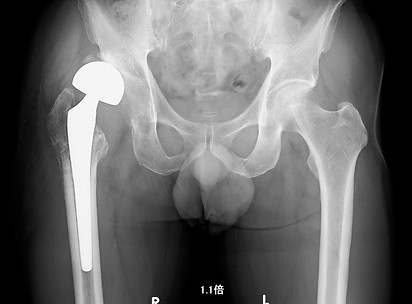

40代女性

両側末期形成不全性股関節症 両股関節をエクセターステム、骨セメントを使用し、再建した。術後14年経過したが、摩耗、弛み、骨粗鬆を認めず元気に働いている。

術後14年